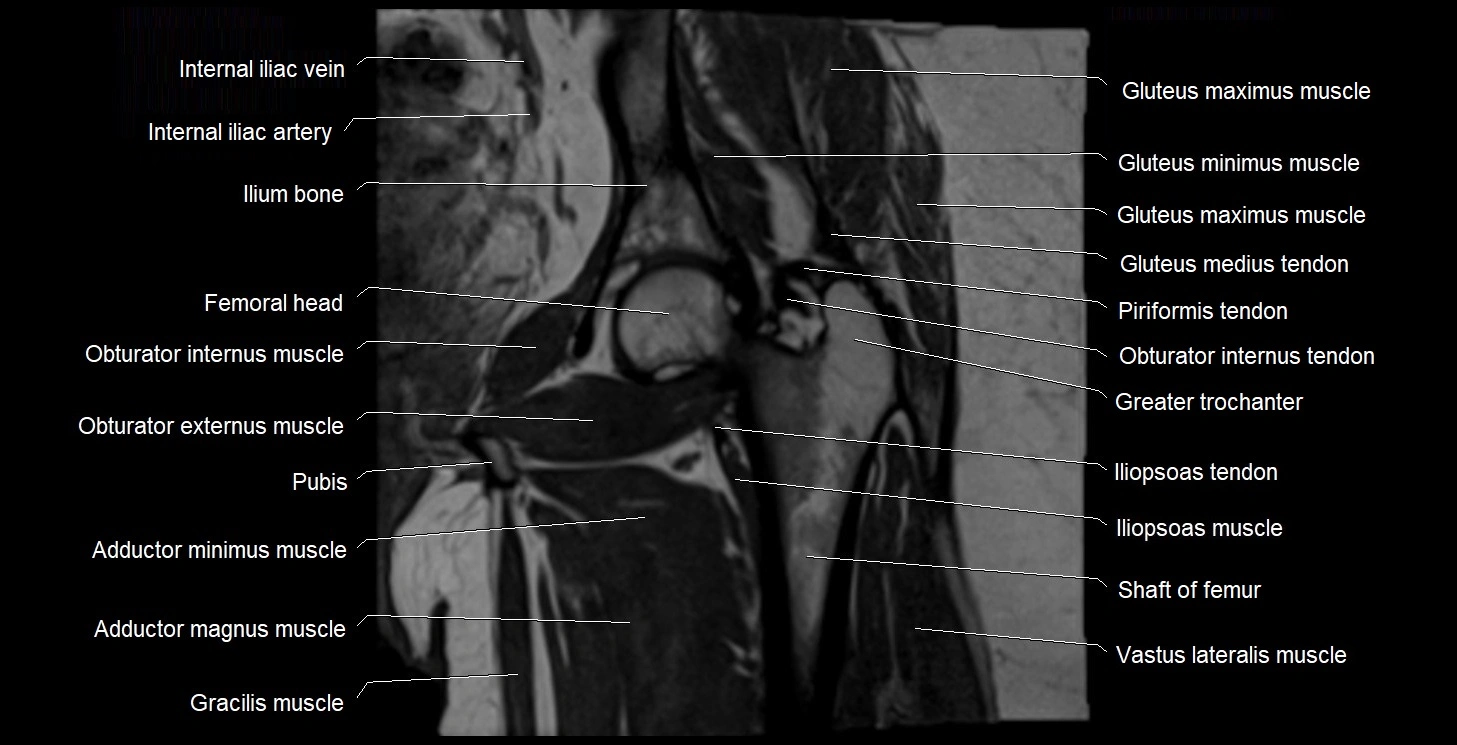

- Gluteus maximus muscle

- Gluteus medius muscle

- Gluteus medius tendon

- Gluteus minimus muscle

- Gracilis muscle

- Greater trochanter

- Head of femur

- Iliopsoas muscle

- Iliopsoas tendon

- Ilium bone

- Internal iliac artery

- Obturator externus muscle

- Obturator internus muscle

- Obturator internus tendon

- Adductor magnus muscle

- Adductor minimus muscle

- Vastus lateralis muscle